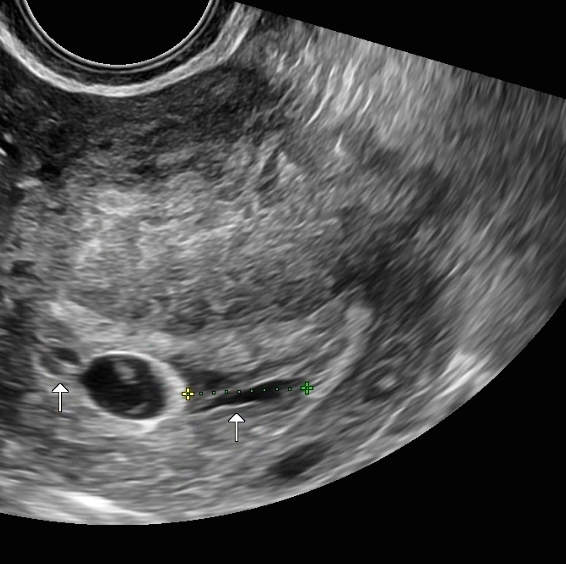

시험관주수 6주 4일 / 예상주수 6주1일 심장박동 확인

📍심장박동은 111bpm이 찍혔다.

6주에 100-120 사이면 정상 수치라고 하셨다

난황은 조금 작아진 느낌이고 아기집은 아주 조금 커진 느낌

난황, 아기집 사이즈는 따로 재주시지 않았지만 그런느낌

아기는 이틀사이에 0.29 -> 0.46 로 조금 컸다 ㅠㅠ

✔️주수에 비해 3일정도 느리다고 하셨다 계속 3일씩 밀리니까 뭔가 불안한마음...

아뮤튼 촘파는 같은병원에서 잰게아니라 정확도는 좀 떨어지는듯 화질차이도 좀 있고 이병원에서는 난황자체가 잘 안보였다